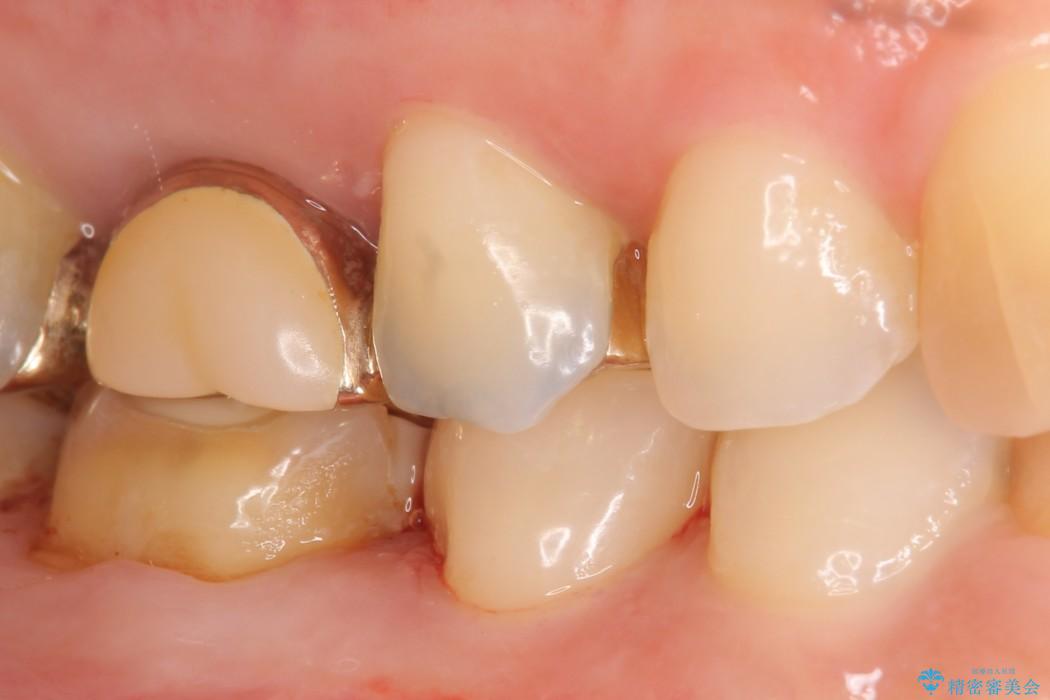

ぱっと見ただけでは特に問題ないように見えますが、レントゲンをよく確認すると詰め物と歯の間に隙間がはっきりと確認ができます。

隙間が発生しているインレー(詰め物)

治療完了した歯でも、時間の経過や力的作用によってセメントが変性したり、隙間が空くことによって詰め物の下に虫歯が発生したりすることがあります。